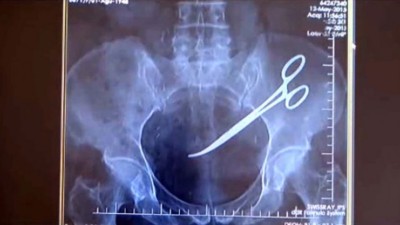

"އެހެންވެ އަހަރެން އެހެން ހޮސްޕިޓަލަކަށް ދެއްކީ. އެތަނުން ބެލި ޑޮކްޓަރު އަހަންނަށް ލަފާ ދިނީ އެކްސްރޭއެއް ނަގަން. އެކްސްރޭ ނެގި އިރު މެޝިން އެލާމް އެޅި. އަދި ޖީބުގައި ކަތުރެއް އޮތް ކަމަށް ޑޮކްޓަރު ބުނި،" ހާނިމް އާއި ހަވާލާދީ ސީއީއެން އިން ބުނެ އެވެ.

އެހެންނަމަވެސް އެއީ ޖީބުގައި އޮތް ކަތުރެއް ނޫން ކަމާއި، އެއީ ހާނިމްގެ ބަނޑުގައި އޮތް "ސާޖިކަލް ކަތުރެއްކަން" ޑޮކްޓަރުންނަށް ފަހުން އެނގިފައިވާ ކަމަށް ވެސް އެ ނޫހުން ބުނެ އެވެ.

ސީއީއެން އިން ބުނީ، ހާނިމްގެ ބަނޑުގައި ރިއްސާ ސަބަބަކީ ބަނޑުގައި އޮތް ކަތުރު ކަމަށާއި، 2010 ވަނަ އަހަރު ހެދި ސާޖަރީގައި ހަރަކާތްތެރިވި ޑޮކްޓަރުންނާ ދެކޮޅަށް ދައުވާ ކުރުމަށް ހާނިމް މިހާރު ނިންމާފައިވާ ކަމަށެވެ.